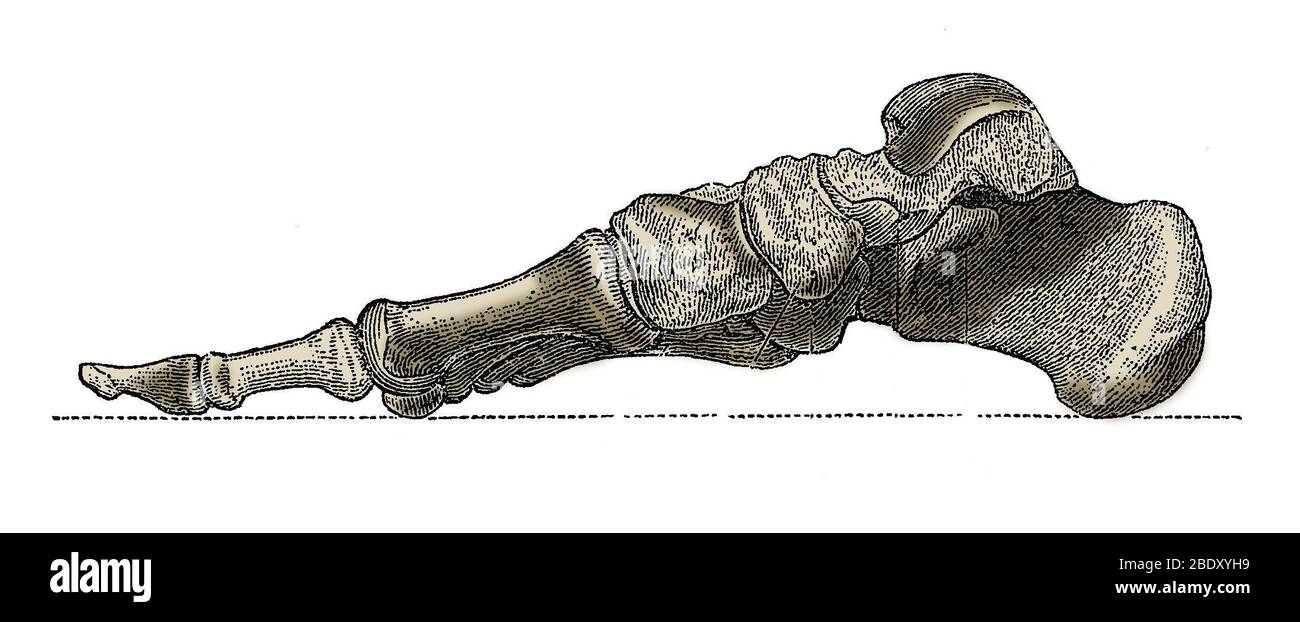

RF2GMNAX6–Vue latérale externe du squelette d'un pied humain articulé, avec la partie distale du tibia et du péroné montés sur un fil. Concept anatomique